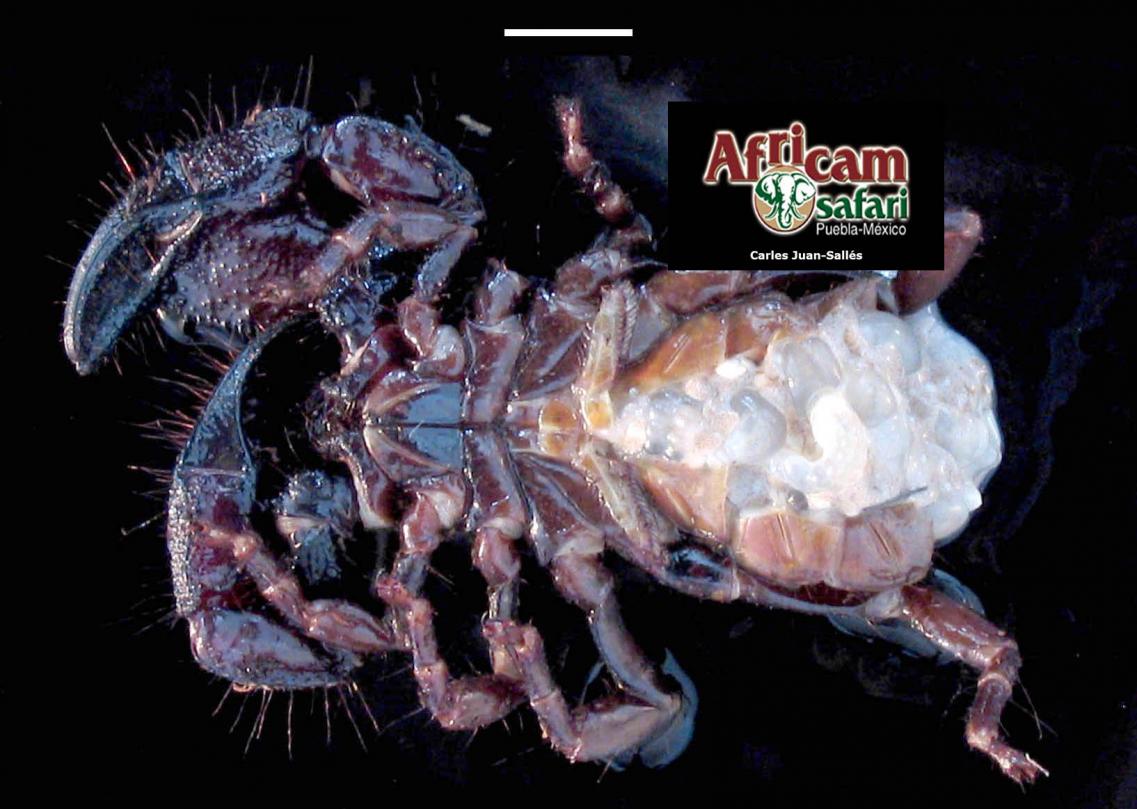

El examen post mortem ofrece una oportunidad única de acceso a todos los tejidos del paciente para diagnóstico de las causas de enfermedad y muerte, y por lo tanto es esencial para medicina preventiva y curativa en grupos de animales, seguimiento de casos, estudios sobre enfermedades, control de zoonosis, medicina de la conservación, y patología forense. En Noah's Path pensamos que un examen post mortem de este tipo de fauna debería ser realizado siempre que sea posible por patólogas/os especializadas/os con el fin de obtener el máximo de información y obtener las muestras más adecuadas.